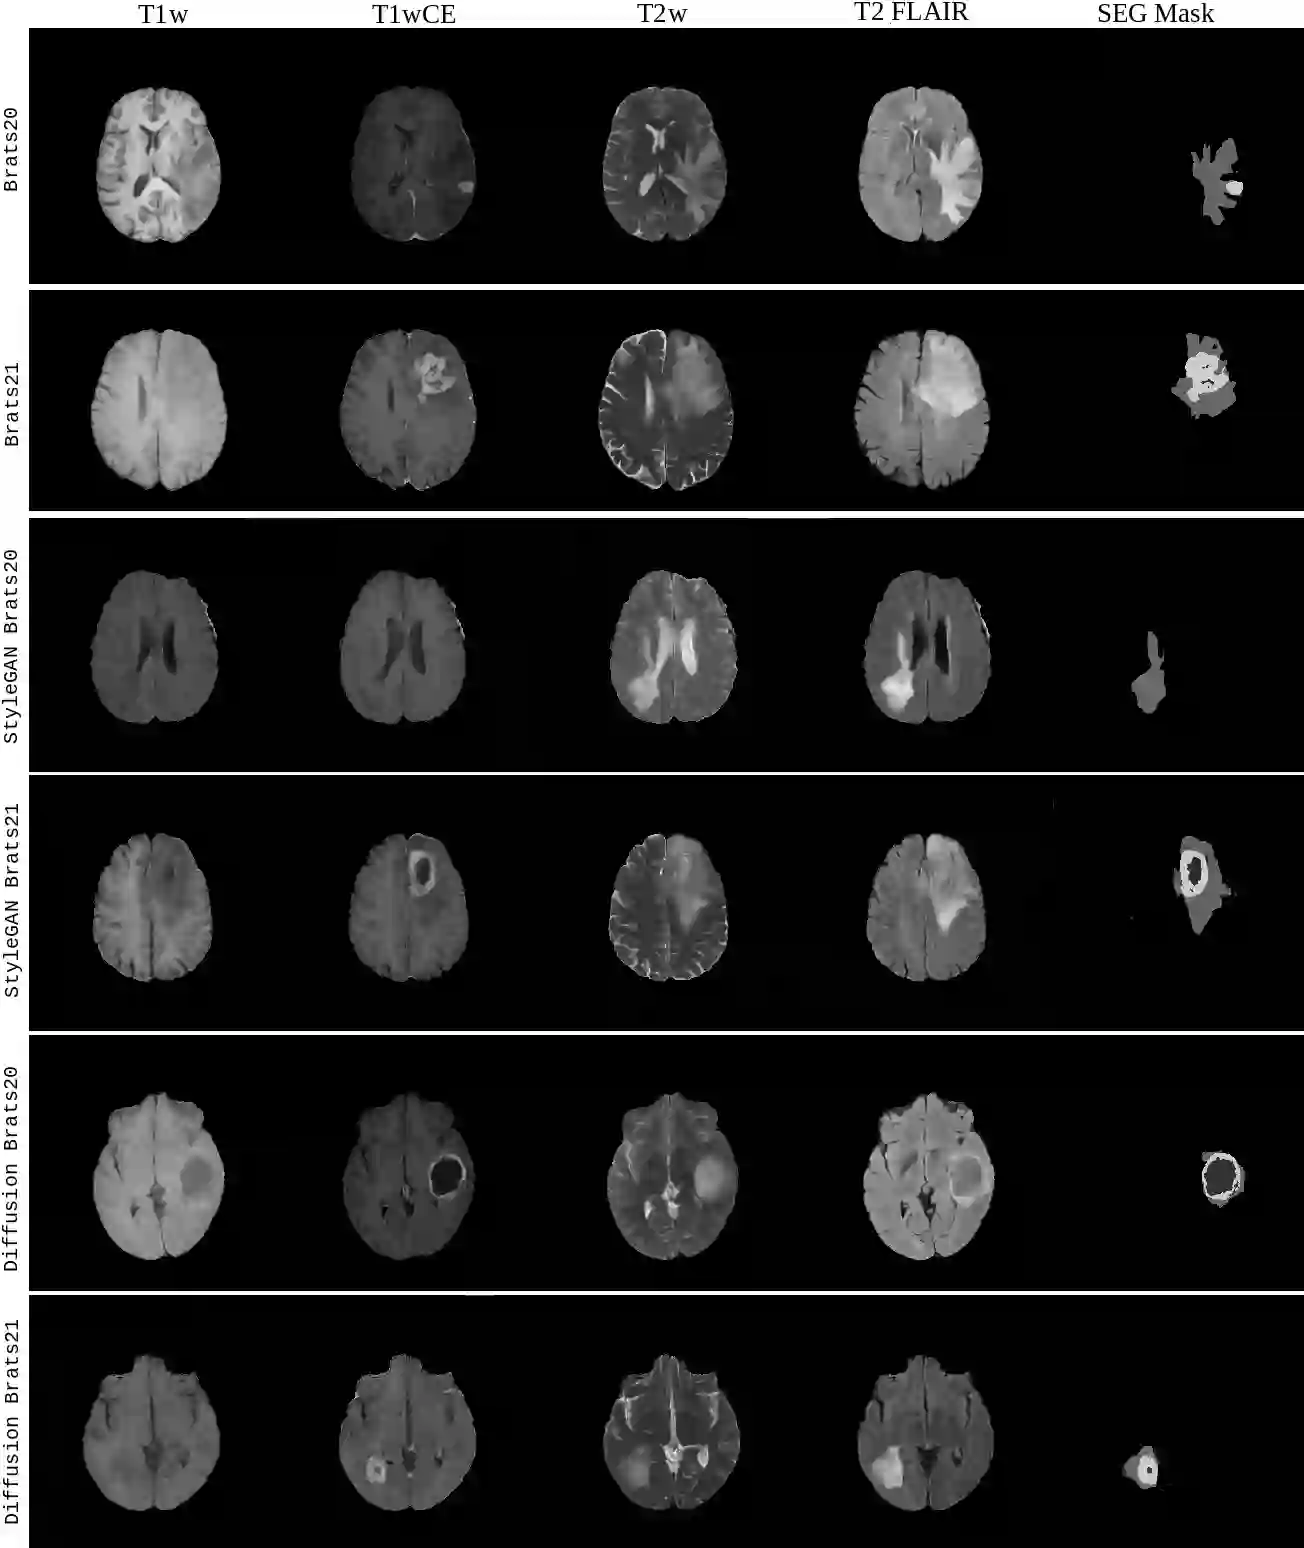

Diffusion models were initially developed for text-to-image generation and are now being utilized to generate high quality synthetic images. Preceded by GANs, diffusion models have shown impressive results using various evaluation metrics. However, commonly used metrics such as FID and IS are not suitable for determining whether diffusion models are simply reproducing the training images. Here we train StyleGAN and diffusion models, using BRATS20 and BRATS21 datasets, to synthesize brain tumor images, and measure the correlation between the synthetic images and all training images. Our results show that diffusion models are much more likely to memorize the training images, especially for small datasets. Researchers should be careful when using diffusion models for medical imaging, if the final goal is to share the synthetic images.